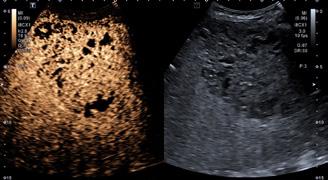

Datorită accesibilităţii si costului mai redus, cele mai utilizate în practica clinică curentă sunt tehnicile elastografice ultrasonografice, anume elastografia tranzitorie unidimensională (VCTE, „vibration controlled transient elastography”)

realizată cu echipamentul Fibroscan® (Echosens, Paris), pSWE (point shear-wave elastography) și 2D-SWE (2D shear-wave elastography), ultimele două fiind integrate în echipamentele ecografice moderne. Principalele caracteristici ale tehnicilor elastografice sunt prezente în Tabelul 1. În prezent, tot mai multe echipamente ultrasonografice dispun de softuri de elastografie și nu doar „vârfurile de gamă”, realizând așa numita „ecografie multiparametrică’’. Atfel, prin integrarea unor module specifice, se realizează cu același echipament ecografia în scară gri, ecografia doppler, ecografia cu contrast, precum și evaluarea elastografică a fibrozei, a steatozei si posibil, a inflamației hepatice [8]

În prezent, tot mai multe echipamente ultrasonografice dispun de softuri de elastografie și nu doar „vârfurile de gamă”, realizând așa numita „ecografie multiparametrică’’. Atfel, prin integrarea unor module specifice, se realizează cu același echipament ecografia în scară gri, ecografia doppler, ecografia cu contrast, precum